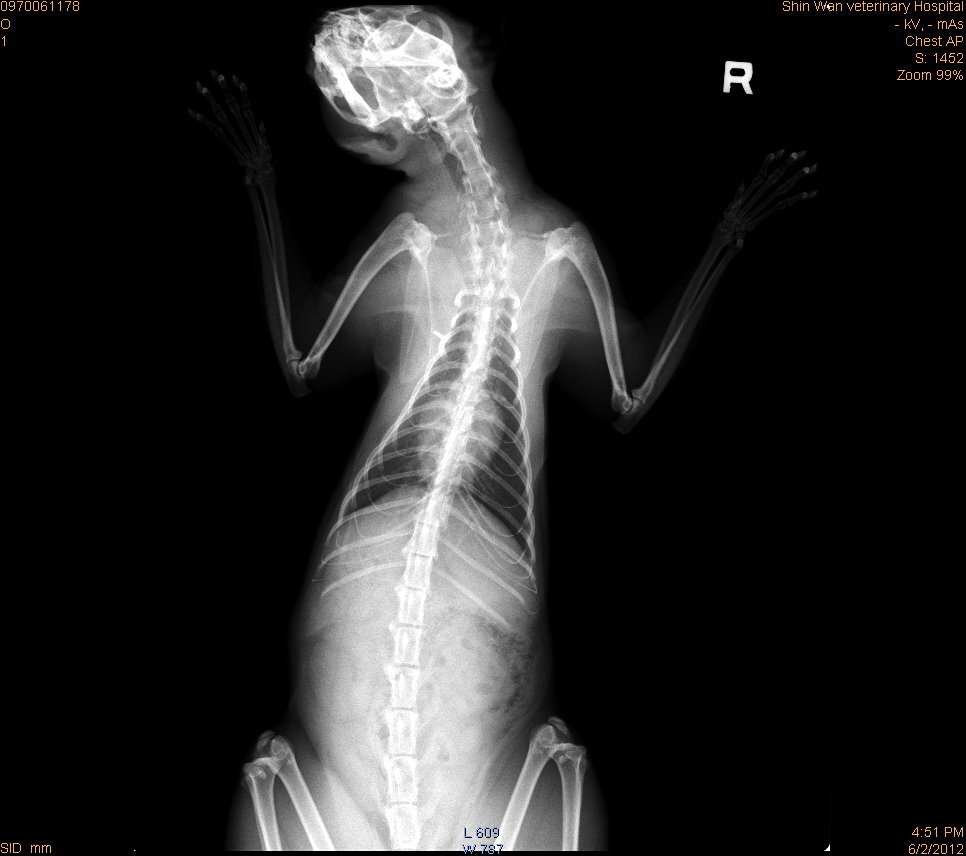

主題: 肩胛骨處爆膿的虎斑貓 申請者姓名: 蔡葦澄 花色: 申請日期: 2012-06-07 23:31:26 申請者部落格: 申請者臉書網址: 所在縣市/合作醫院: 台北市/欣旺動物醫院 治療費用: 3500元 需求人數: 9人 已結案 (2012-12-01 19:56:05) 報名人員: 靜小芳(已付款)、Linda Wang(已付款)、私はお 金が要ります(已付款)、黃美菁(已付款)、blue(已付款)、九妹(已付款)、Yang Ying Ling(已付款)、張智麟、小蘋果(已付款)、私はお 金が要ります、小舟(已付款)、 候補人員: 小舟、 動物病情說明: 大道里捕捉的虎斑大公貓,本來只是要結紮,麻醉後發現右肢肩胛骨突出且有不明腫塊,切開後發現感染嚴重、爆膿,形成一個空腔,清創後將傷口縫合,並照X光確認骨頭部分無異常,公貓沒有結紮常常會打架、爭地盤,落得滿身是傷,不小心發炎變成蜂窩性組織炎,嚴重感染可能會導致死亡,所以公母貓都需要結紮,除了不會繁衍下一代,更可以維護生活品質,貓咪後續需兩週抗生素治療,就可以R回原地。醫療費用還請各位幫忙。